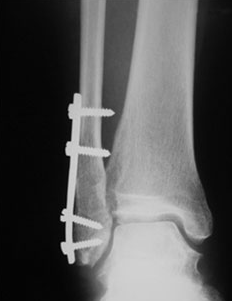

2. 외과 골절

발 관절이 강하게 바깥쪽으로 비틀어지게 되면 거골에 밀려 외과골절이 발생할 수 있고, 이는 나선형으로 꺾이는 경우가 많습니다. 뼈가 어긋남이 없다면 깁스등의 보존적 치료가 가능하며, 어긋남이 심하다면 플레이트와 나사등을 이용하여 고정하는 수술을 할 가능성이 있습니다.